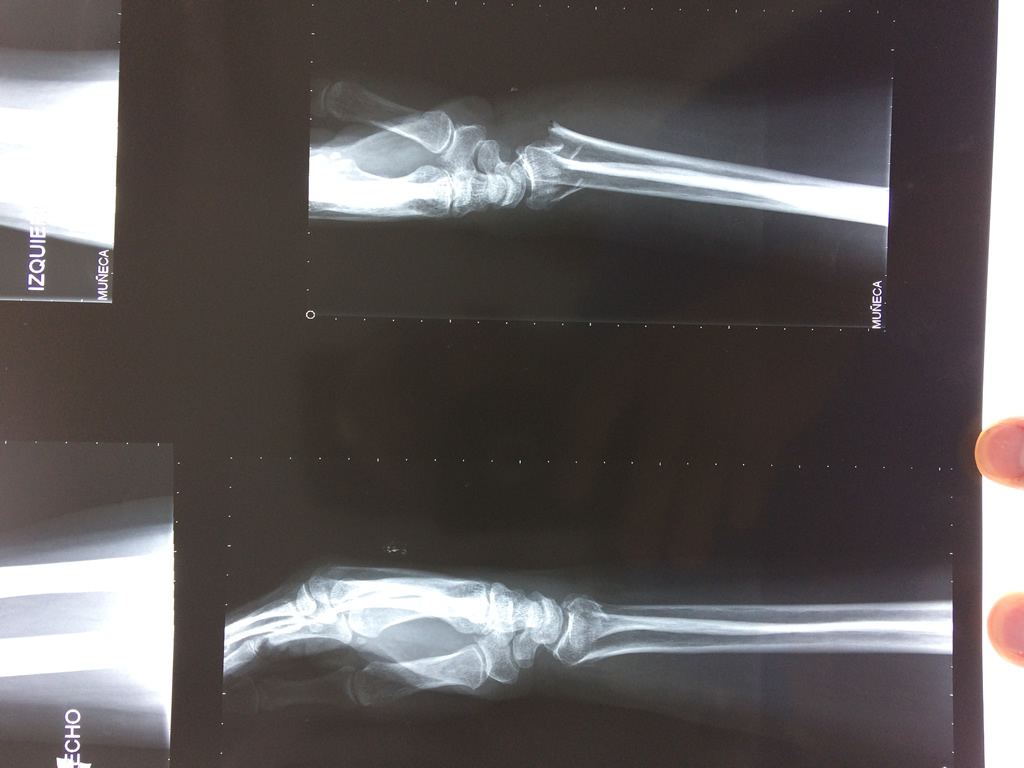

Calcaneo - Cirugías de Muñecas y Manos

Los procedimientos más comunes en cirugía de la mano son aquellos destinados a reparar traumatismos, incluyendo lesiones de tendones, nervios, vasos sanguíneos, y articulaciones; huesos fracturados; y quemaduras, cortes, y otros daños de la piel.